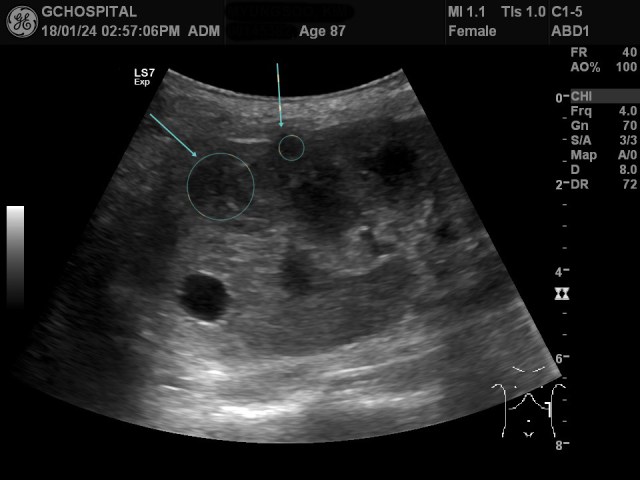

환자는 흉벽에 꽤 심한 통증을 호소하고 있었기 때문에 누워있는 자세에서만 신장을 확인했기 때문에 이런 병변을 놓쳤을지도 모른다는 판단을 했고, 이번에는 아프더라도 참으라고 당부한 다음 Rt. decubitus position에서 다시 복부초음파에 사용하는 curvilinear probe를 사용해서 앞서의 종괴와 8미리 크기의 단순낭종이 있던 부위를 스캔한 게 위 영상입니다(마커에서는 누워있는 상태로 표시됬지만, decubitus position에서 스캔한 영상입니다).

앞서 봤던 8미리크기의 단순낭종은 희미하게 보이지만, 앞서 보였던 2.5센티미터 크기의 고형성 종괴는 여전히 뚜렷하게 확인이 되지 않고 있습니다.

앞서 선형탐촉자에서 보였던 고형성종괴와 단순낭종의 위치는 위 영상에서 파란색 원으로 표시한 부위쯤이 되겠습니다. 이걸 알고 다시 바로 위의 영상을 보면 어느정도 병변이 있을 가능성을 짐작하는건 가능합니다.

여기서 먼저 반성하고 넘어갈 부분이 있습니다. 제가 초음파검사를 하면서 해당 병변이 위치하고 있는 쪽에 정확히 focus를 조정하고, 해당 병변이 위치하는 쪽에 depth를 맞춰서 확대한 영상으로 봤더라면 굳이 curvilinea probe라 하더라도 2센티미터 넘는 병변을 못보고 놓치는 일은 없었을지도 모른다는 점이지요.